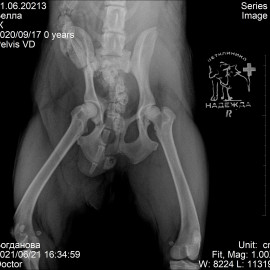

Собака по кличке Белла из города Мурманск. Её сбила машина. после чего были жалобы на потерю опороспособности на тазовые конечности. При пальпации живота отмечался дефект. После проведения рентгенологического исследования были поставлены диагнозы: вывих правого тазобедренного сустава, травматическая грыжа живота, множественные переломы костей таза. Были проведены операции: остеосинтез костей таза, остеосинтез правого тазобедренного сустава (установлен протез круглой связки), герниотомия травматической грыжи живота.

Снимок 1-2 до операции.